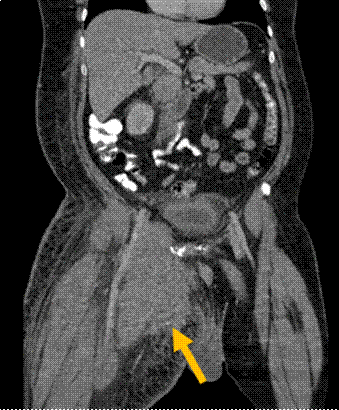

Se realiza tomografía computada de tejidos blando en la que se observa gran lesión con realce homogéneo del contraste que se extiende desde la región inguinal hasta la región anterior medial del muslo derecho proximal, asociado a cambios inflamatorios en tejidos blandos, de 20.2 x 10.5 x 15.2 cm en sus ejes longitudinal, antero posterior y transverso (Figuras 1 y 2).